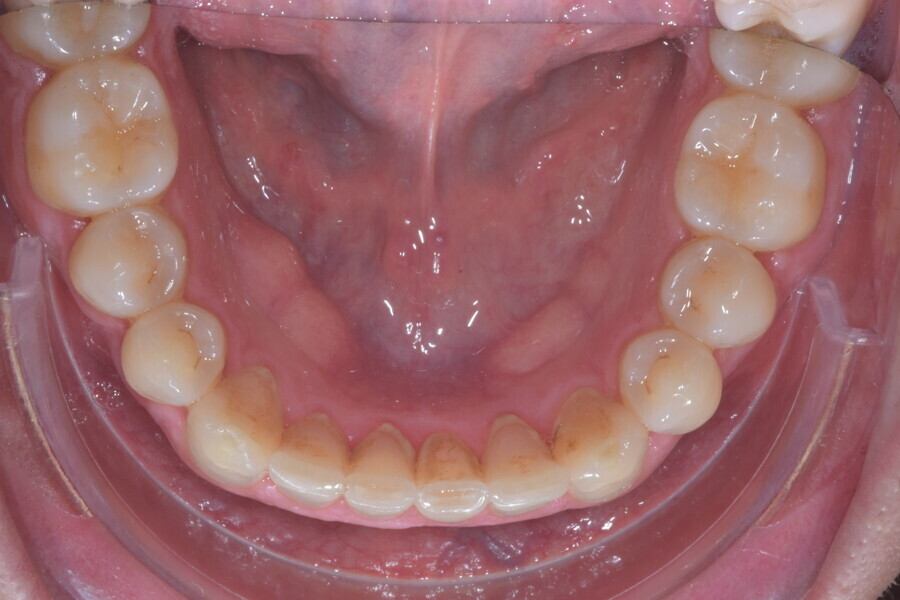

A 37-year-old male patient presented with the chief need for re establishing anterior alignment in both arches. Facial analysis showed a short face with a flat profile but proper chin projection (Figs. 9–12), and clinical examination revealed a skeletal Class I (ANB = 0.89°) and dental Class I malocclusion with severe deep bite (almost 100%), a deep curve of Spee, normal maxillary central incisor torque (Ui–FH = 110°), mild maxillary crowding and moderate mandibular crowding (Figs. 13–18). The deep bite components were represented in this patient by the severe skeletal condition of hypo divergent pattern (FMA = 14.24°) with normal maxillary and mandibular incisor inclination and decreased gonial angle (110.46°). Analysis of the cephalometric radiograph indicated a reduced lower anterior facial height, combined with a hypo-divergent pattern (Fig. 19). The only treatment option suggested was orthodontic treatment with aligners for deep bite correction with all the features described (bite ramps, pressure area, 3D curve of Spee levelling, Class II elastics and heavy occlusal contacts).

The digital treatment plan (ClinCheck) provided 12 aligners for the maxillary arch and 17 for the mandibular arch. The treatment objectives were focused on coupled vertical movements of posterior extrusion and anterior intrusion by means of bite ramps, providing for posterior disocclusion and anterior intrusion of mandibular teeth by means of extrusion attachments needed for mandibular arch levelling. The maxillary and mandibular incisors were proclined to level the upper and lower curve of Spee and to support the flat profile and the lips. Class II elastics were planned to support mandibular proclination and heavy posterior occlusal contacts with relative posterior extrusion. Lateral and posterior maxillary torque were planned to be close to 0°, to achieve wider arch design and ideal intercuspation. No digital over-engineering was planned in the set-up. Because of the age of the patient, the aligners were changed every ten days for a treatment time of less than six months. At the end of the first stage of aligners (Figs. 20–24), an additional stage was planned to improve molar intercuspation without elastics with a digital plan of five further aligners. This brought the total treatment time to 7.5 months since the additional aligners were changed every week.

At the end of the treatment, Class I canine and molar relationships were obtained, maxillary incisor inclination was slightly increased (Ui–FH = 112°), mandibular incisor inclination (IMPA = 97.09°) was fully corrected by means of proclination and the divergency was slightly increased (SN–GoGn = 27°) because of the relative posterior extrusion and use of Class II elastics—a small variation (1°), which is interesting considering the age of the patient (Figs. 25–35). A balanced smile arc was obtained with an ideal relationship between the maxillary incisors and lower lip, and torque control of the lateral and posterior segments generated a broader smile.